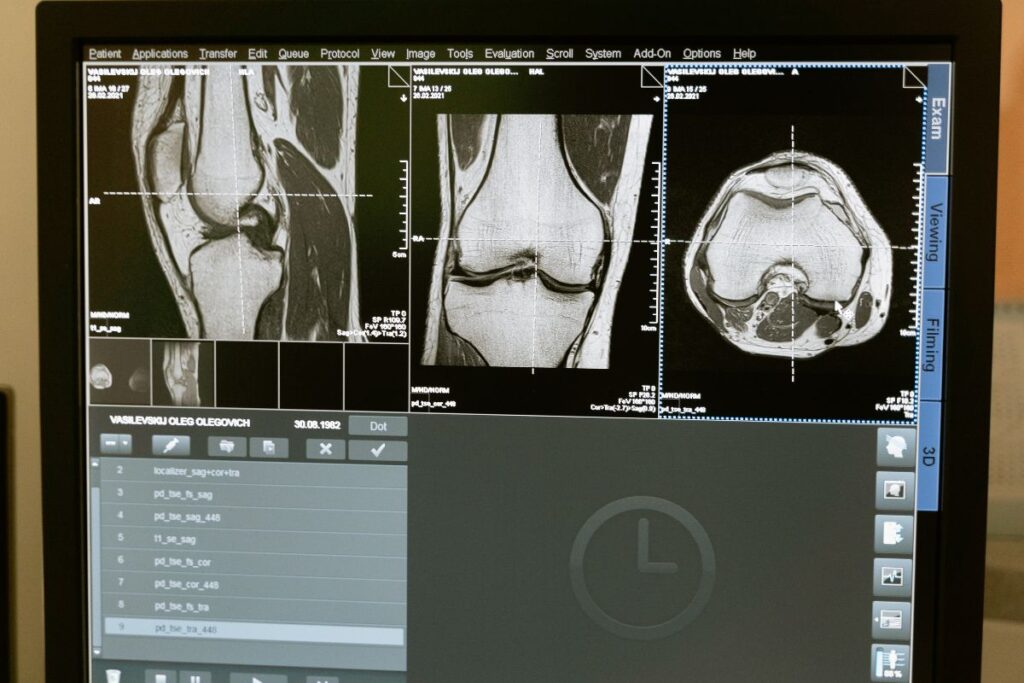

For the majority of cases, MRIs are used to exam the brain, spinal cord, or cardiovascular systems. However, they can be used for a range of further purposes and there are various reasons why your doctor might have booked you in to receive a scan. MRIs can be used to examine internal organs such as the liver, kidneys, or pancreas, and check for abnormalities including tumours. They are also useful for looking at bones, joints, and, muscles, where they can be used to assess the extent of damage caused by trauma or accidents.